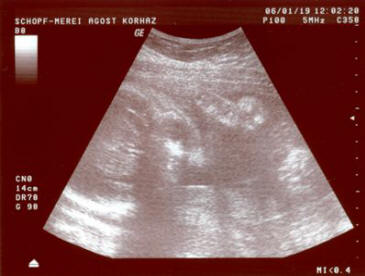

Születés előtti UH adatok